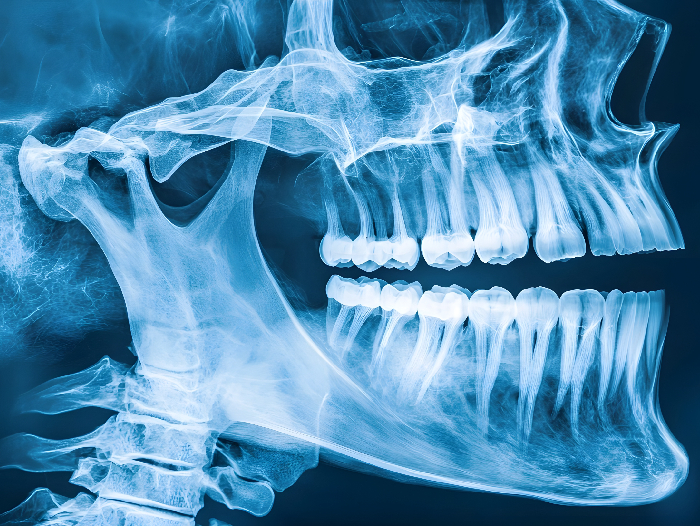

The research team involved in the European project HYDROHEAL is developing microparticles encapsulated in bioresorbable and self-hardening hydrogels, capable of incorporating and transporting a range of pharmacological agents. These biomaterials will act as temporary scaffolds to support bone regeneration while also enabling the controlled and targeted release of active agents, thereby enhancing treatment effectiveness and significantly reducing the risk of infection and implant rejection. The project focuses on developing new biomaterials for treating vertebral and alveolar fractures (in the jawbone, at the base of the teeth), particularly in complex cases resulting from osteoporosis, cancer or trauma.

At the Universitat Politècnica de Catalunya - BarcelonaTech (UPC), the project is coordinated by ICREA Research Professor Conrado Aparicio, head of the Bioinspired Oral Biomaterials and Interfaces (BOBI) research group and a researcher at the UPC’s Department of Materials Science and Engineering. As Aparicio explains, “the materials currently used to replace bone are often prone to infection. To address this, the materials developed in the project will incorporate antibacterial agents. Our group will assess how bacteria adhere to the developed materials under conditions that simulate the human body, enabling us to determine the best strategies to prevent this type of bone infection.”